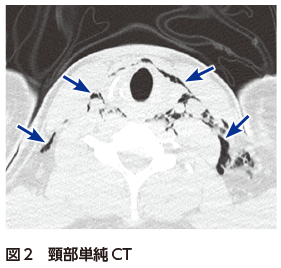

解答・解説】持続する激しい胸痛で救急搬送された20歳代男性

解答・解説】持続する激しい胸痛で救急搬送された20歳代男性